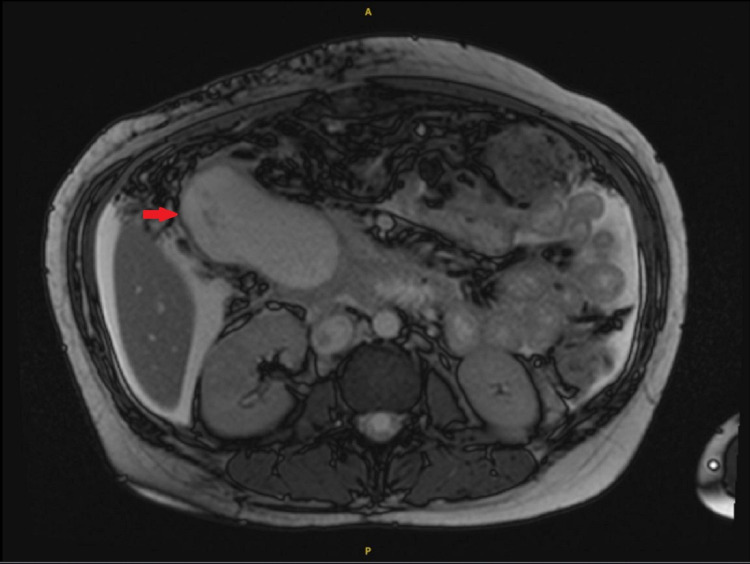

CT scan of the abdomen and pelvis with contrast revealed features of chronic pancreatitis along with a 7 x 4.5-cm fluid collection inferior to the uncinate process of the pancreas with intra and extrahepatic biliary dilatation. MRI of the pancreas and abdomen confirmed findings of 8 x 6 x 6-cm pseudocyst in the pancreatic head causing mass effect (Figure 1), leading to marked dilatation of the pancreatic duct (PD) at about 6 mm, prominent common bile duct (CBD) of about 11 mm with dilatation of the intrahepatic biliary tree. Moderate ascites was also seen.